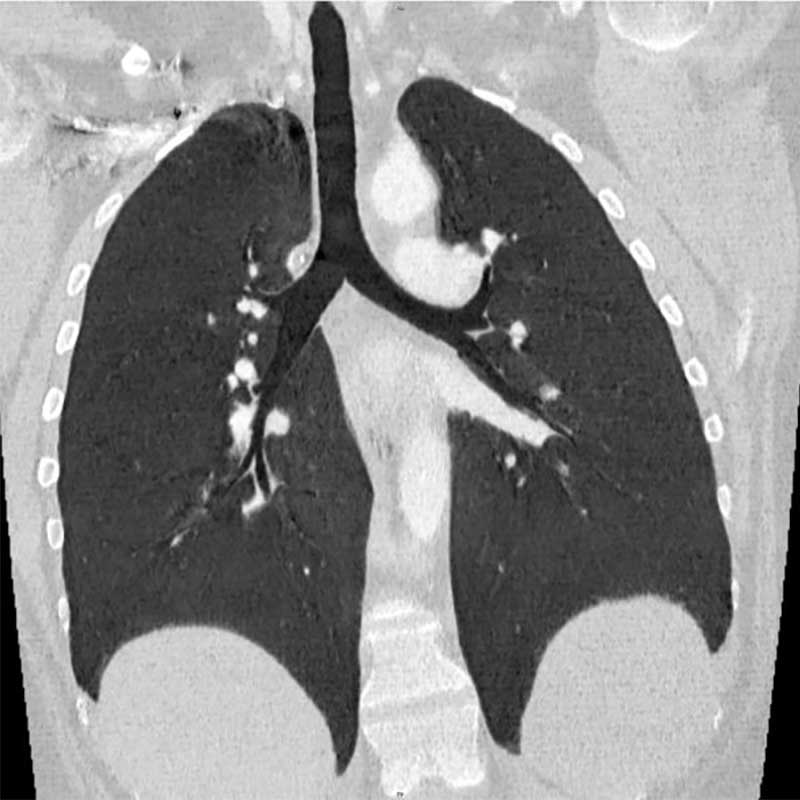

Hochspezialisierte Modalitäten (Volldigitales Röntgen, 80-Zeilen Multidetektor Spiral-CT, 3-Tesla MRT) wenden in ihrer Rekonstruktions-Software sowie nachgeschalteten diagnostische Algorithmen künstlicher Intelligenz an und gewährleisten eine hoch akkurate Diagnostik bei schonender Patientenversorgung. Neben Methoden zur automatischen Detektion und Volumetrie pathologischer Areale kommen Untersuchungsverfahren zur Lungenperfusion und -ventilation zum Einsatz. Die CT-gesteuerte Bronchusnavigation wird neben anderen Methoden als minimal-invasives Biopsieverfahren eingesetzt. Bei diesem Bildfusionsverfahren fungieren hoch aufgelöste CT-Datensätze als interaktive Karte (Roadmap) zur bronchoskopischen Biopsiegewinnung und ergänzen neben der CT-gesteuerten transthorakalen Biopsie die Kryobiopsie und offene Lungenbiopsie-Verfahren.

Die Diagnostik beginnt mit einer professionellen Befragung (Anamnese) und klinischen Untersuchung. Viele Faktoren werden berücksichtigt – u.a. die berufliche und örtliche Umgebung, die Vorgeschichte, Hobbys und die Verwendung legaler oder illegaler Drogen. Standarduntersuchungen sind: Blutuntersuchungen, Lungenfunktionsdiagnostik, Thorax-CT und Bronchoskopie. Eine Lungenbiopsie kann nach Beurteilung des ILD-Boards notwendig werden. Die Biopsie, die Entnahme von Lungengewebe, und nachfolgende histologische Aufarbeitung beim Pathologen gelten jedoch nicht mehr als einzige Methode der Diagnosesicherung. Sie ist – neben klinischer Informationen und Computertomographie – eine von drei validen Methoden, die das ILD-Board gewichtet, heranzieht und abstimmt.

Die Sarkoidose ist die häufigste Erkrankung des Lungengerüstes überhaupt. Patientinnen und Patienten suchen regelmäßig mit pulmonalen Symptomen wie Luftnot oder Husten die Lungenfachärztin bzw. den Lungenfacharzt auf. Fast bei der Hälfte aller Fälle werden die Granulome jedoch als Zufallsbefund bei symptomfreien Patientinnen und Patienten entdeckt. Das Röntgenbild der Lunge löst dann weitere Tests aus bzw. die computertomographische Bildgebung. Die Erkrankung lässt sich nicht regelhaft an einem Röntgenbild allein diagnostizieren.

Es gibt vielfältige morphologische Erscheinungsbilder der Erkrankung in der Lunge mit Überlappungen zu anderen Erkrankungen. Die Diagnose in der Computertomographie kann deshalb anspruchsvoll sein. Dabei ist unklar, warum sich die Sarkoidose im Einzelfall so unterschiedlich verhält – abgesehen von der Frage der Organbeteiligung. Die Verlaufsformen werden in akut oder chronisch eingeteilt. Akute Formen der Sarkoidose beginnen häufig mit Gewichtsverlust, Abgeschlagenheit, Nachtschweiß oder Temperaturen 37,5°C bis 37,9°C (subfebril). Die Kombination von Gelenkschmerzen, bläulichem Hautausschlag und Fieber ist als sogenanntes Löfgren-Syndrom bekannt. Entzündungsparameter im Blutserum schließen eine erhöhte Konzentration von Interleukin-2-Rezeptoren ein. Die akute Sarkoidose betrifft neben der Lunge oft weitere Organe, z.B. lymphatische Organe, Milz, Leber und Knochenmark. Akute Verlaufsformen ohne Beteiligung der Milz tendieren zur Spontanheilung (Spontanremission). Wiederauftreten (Rezidive) manifestiert sich hingegen meistens mit akuten Symptomen.

Die Diagnose erfolgt anhand: typischer Hautveränderungen, Lymphknotenvergrößerungen, morphologischer Veränderungen der Lunge in der Computertomographie und / oder des Nachweises von Sarkoidose-Granulomen im Gewebe. Besonders die Abgrenzung zu anderen Systemerkrankungen kann erhebliche Probleme aufwerfen, auch nach histologischer Abklärung. Das spezialisierte ILD-Board entscheidet interdisziplinär, welche diagnostische Methode wir im Einzelfall heranziehen.